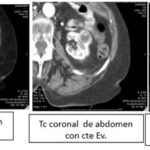

Se trabajó bajo un diseño no experimental, lo que significa que no hubo manipulación de variables, bajo un enfoque horizontal retrospectivo, descriptivo y observacional, donde se empleó la tomografía computada como método diagnóstico principal para el diagnóstico de lesiones quísticas renales. Se utilizó el tomógrafo PHILIPS ACCESS CT (Anexos 13, 14 y 15), emitiendo 16/32 cortes, realizado por médicos especialistas en diagnóstico por imágenes, siguiendo la clasificación Bosniak para categorizar cada uno de los 523 quistes estudiados y poder distinguir por medio del uso de contrastes si correspondían a quistes simples ubicados en la categoría I o a quistes complicados o malignos, los cuales se ubican en las categorías III y IV de Bosniak.

TC: es la técnica de elección para la caracterización de las lesiones renales. El protocolo para el estudio de lesiones renales constará de:

- Fase nefrográfica o parenquimatosa: a los 80-120 segundos. Es la fase más eficaz en el estudio de masas renales de menor tamaño.

- Fase excretora (opcional): a partir de los 180 segundos. Útil en sospecha de invasión del aparato excretor y para la planificación quirúrgica en cirugías conservadoras.